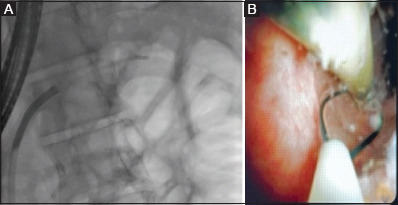

背景:胰腺支架近端移位是一个不常见但重要的问题,它会带来疼痛和胰腺炎的风险。对于内窥镜医生来说,这通常是一个具有挑战性的情况,10%的病例需要手术切除。方法:对2010年1月至2019年12月在印度北部一家三级医疗中心进行的支架移除手术进行了10年的回顾性研究。结果:本组共16例(平均年龄39.52岁,男性13例[81.25%])行近端移位胰内支架(pmps)。13例(81.25%)患者胰管扩张,3例(18.75%)患者胰管未扩张。在大多数患者中,pmps位于膝(50%),62%长度为10 cm。3例(18.75%)患者支架碎片化,其余13例(81.25%)患者支架原位完整。12例(75%)患者可以完全取出PPMS和支架碎片,大多数(50%)患者使用抓钳。在支架碎片化和定位困难的患者中(n=3),胰镜辅助技术可将支架或碎片取出。3例患者pmps无法检索:所有这些失败都发生在我们单位没有SpyGlass胰镜的研究期间。2例患者(12.5%)报告术后疼痛对静脉镇痛药有反应。结论:内镜下取下近端移位支架,结合技术和附件是安全有效的。胰镜检查提高了成功率。支架移除很少需要手术。

Results: Sixteen patients (mean age 39.52 years, 13 [81.25%] males) with proximally migrated pancreatic stents (PMPSs) were studied. Thirteen (81.25%) patients had a dilated pancreatic duct (PD) and 3 (18.75%) had a non-dilated PD. In the majority of patients, the PMPSs were located at the genu (50%), while 62% were 10 cm in length. Three (18.75%) patients had fragmented stents, whereas the remaining 13 (81.25%) had intact stents in situ. Complete retrieval of the PPMS and stent fragments was possible in 12 (75%) patients, with grasping forceps being used in the majority (50%). In patients with fragmented stents and difficult locations (n=3), pancreatoscopy-assisted techniques resulted in the retrieval of the stent or fragments. PMPSs could not be retrieved in 3 patients: all these failures were during the study period when a SpyGlass pancreatoscope was not available in our unit. Two patients (12.5%) reported post-procedural pain that responded to intravenous analgesics.